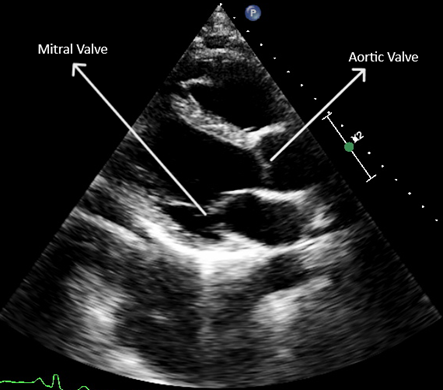

We are training an AI to automatically detect and assess the clarity of valve visibility in echocardiographic images, specifically in the Parasternal Long Axis (PLAX) view.

To achieve this, we are ranking images based on how clearly each valve — mitral or aortic — is visible, from the most clearly visible to the least visible.

We address the mitral and aortic valves separately.

Visual Example

PLAX Valve Visibility Example